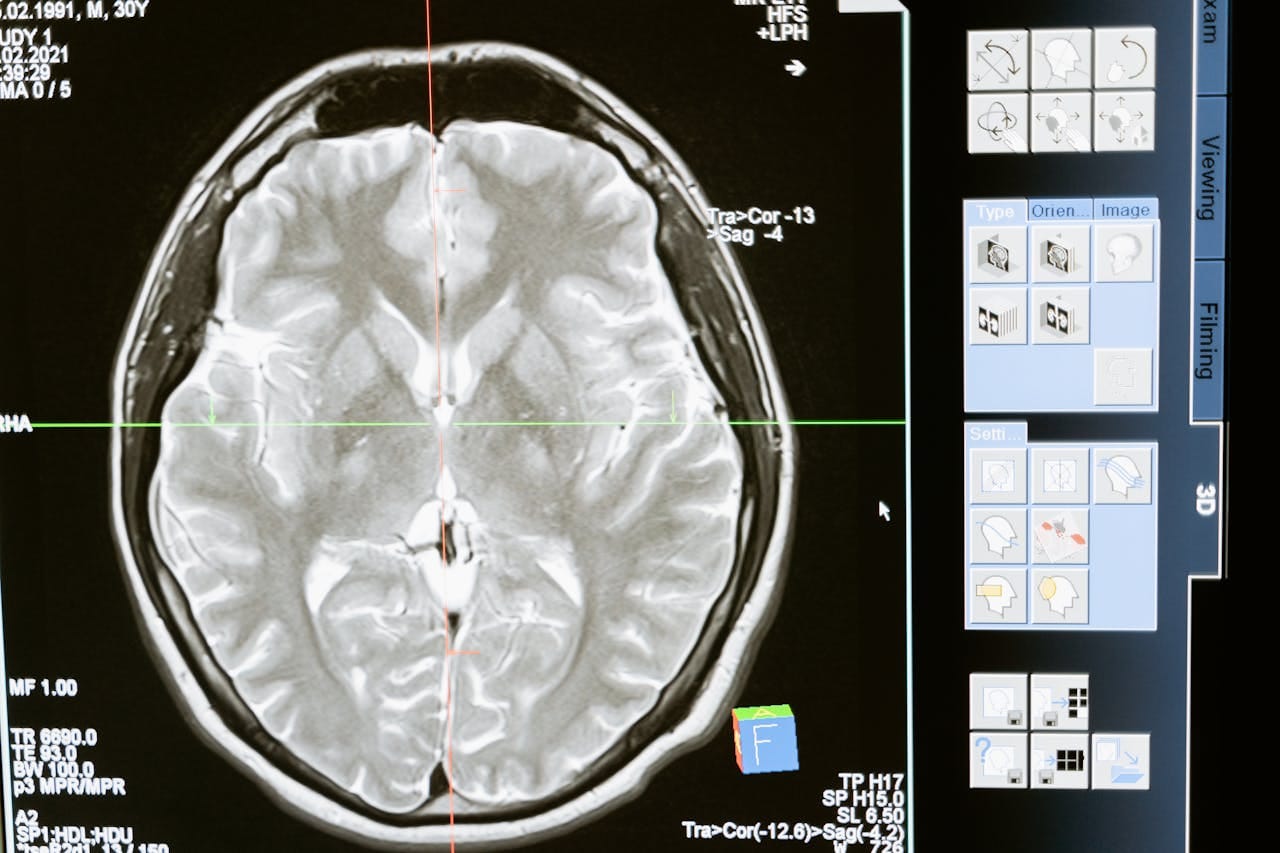

AI-powered diagnostics have been making headlines for their ability to detect diseases like cancer, heart conditions, and even rare disorders.

Machines trained on vast datasets can often spot subtle patterns in imaging or lab results faster than human eyes.